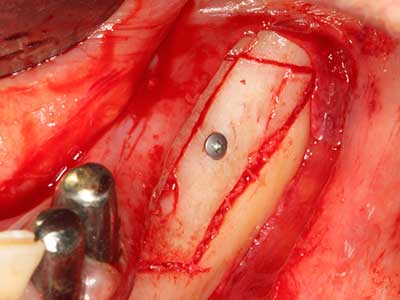

Fig. 18: preparazione di una copertura corticale con sega piezoelettrica per osso (Piezomed, W&H).

Fig. 19: sito chirurgico dopo neurolisi e rimozione dell'osteoma.

Fig. 20: la copertura ossea rimossa viene riadattata e fissata con una vite per osteosintesi (KLS Martin, Tuttlingen).